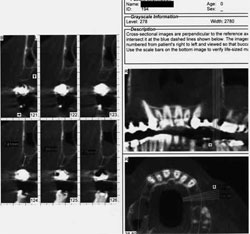

Next the patient was referred for a cone-beam tomography scan of the maxilla to evaluate the alveolar dimensions and the maxillary antra, which were thought to be inadequate (Figure 10 and Figure 11). Because radiographic studies showed maxillary sinus thickening, the patient was referred to his otolaryngologist, whose diagnosis was: "rule out ethmoid sinusitis, bilateral maxillary sinusitis with sinus cyst." Subsequent procedures were: "ethmoidectomy, bilateral revision, endoscopic, maxillary sinusotomy, endoscopic revision and ENTrak," after which the patient was cleared to proceed with sinus elevation surgery.

Cone-beam evaluation revealed approximately 5 mm of alveolar bone on the right. Because the right side demonstrated inadequate bone dimensions for simultaneous placement of implants, a lateral window sinus graft was completed first. Removing the existing bridge beforehand was not necessary because access was not impeded.13,14The lateral window-type sinus elevation was therefore performed using a combination of xenograft and allograft (Figure 12).

Figure 10 Preoperative cone-beam scan, right side. |  Figure 11 Preoperative cone-beam scan, left side. | |||||